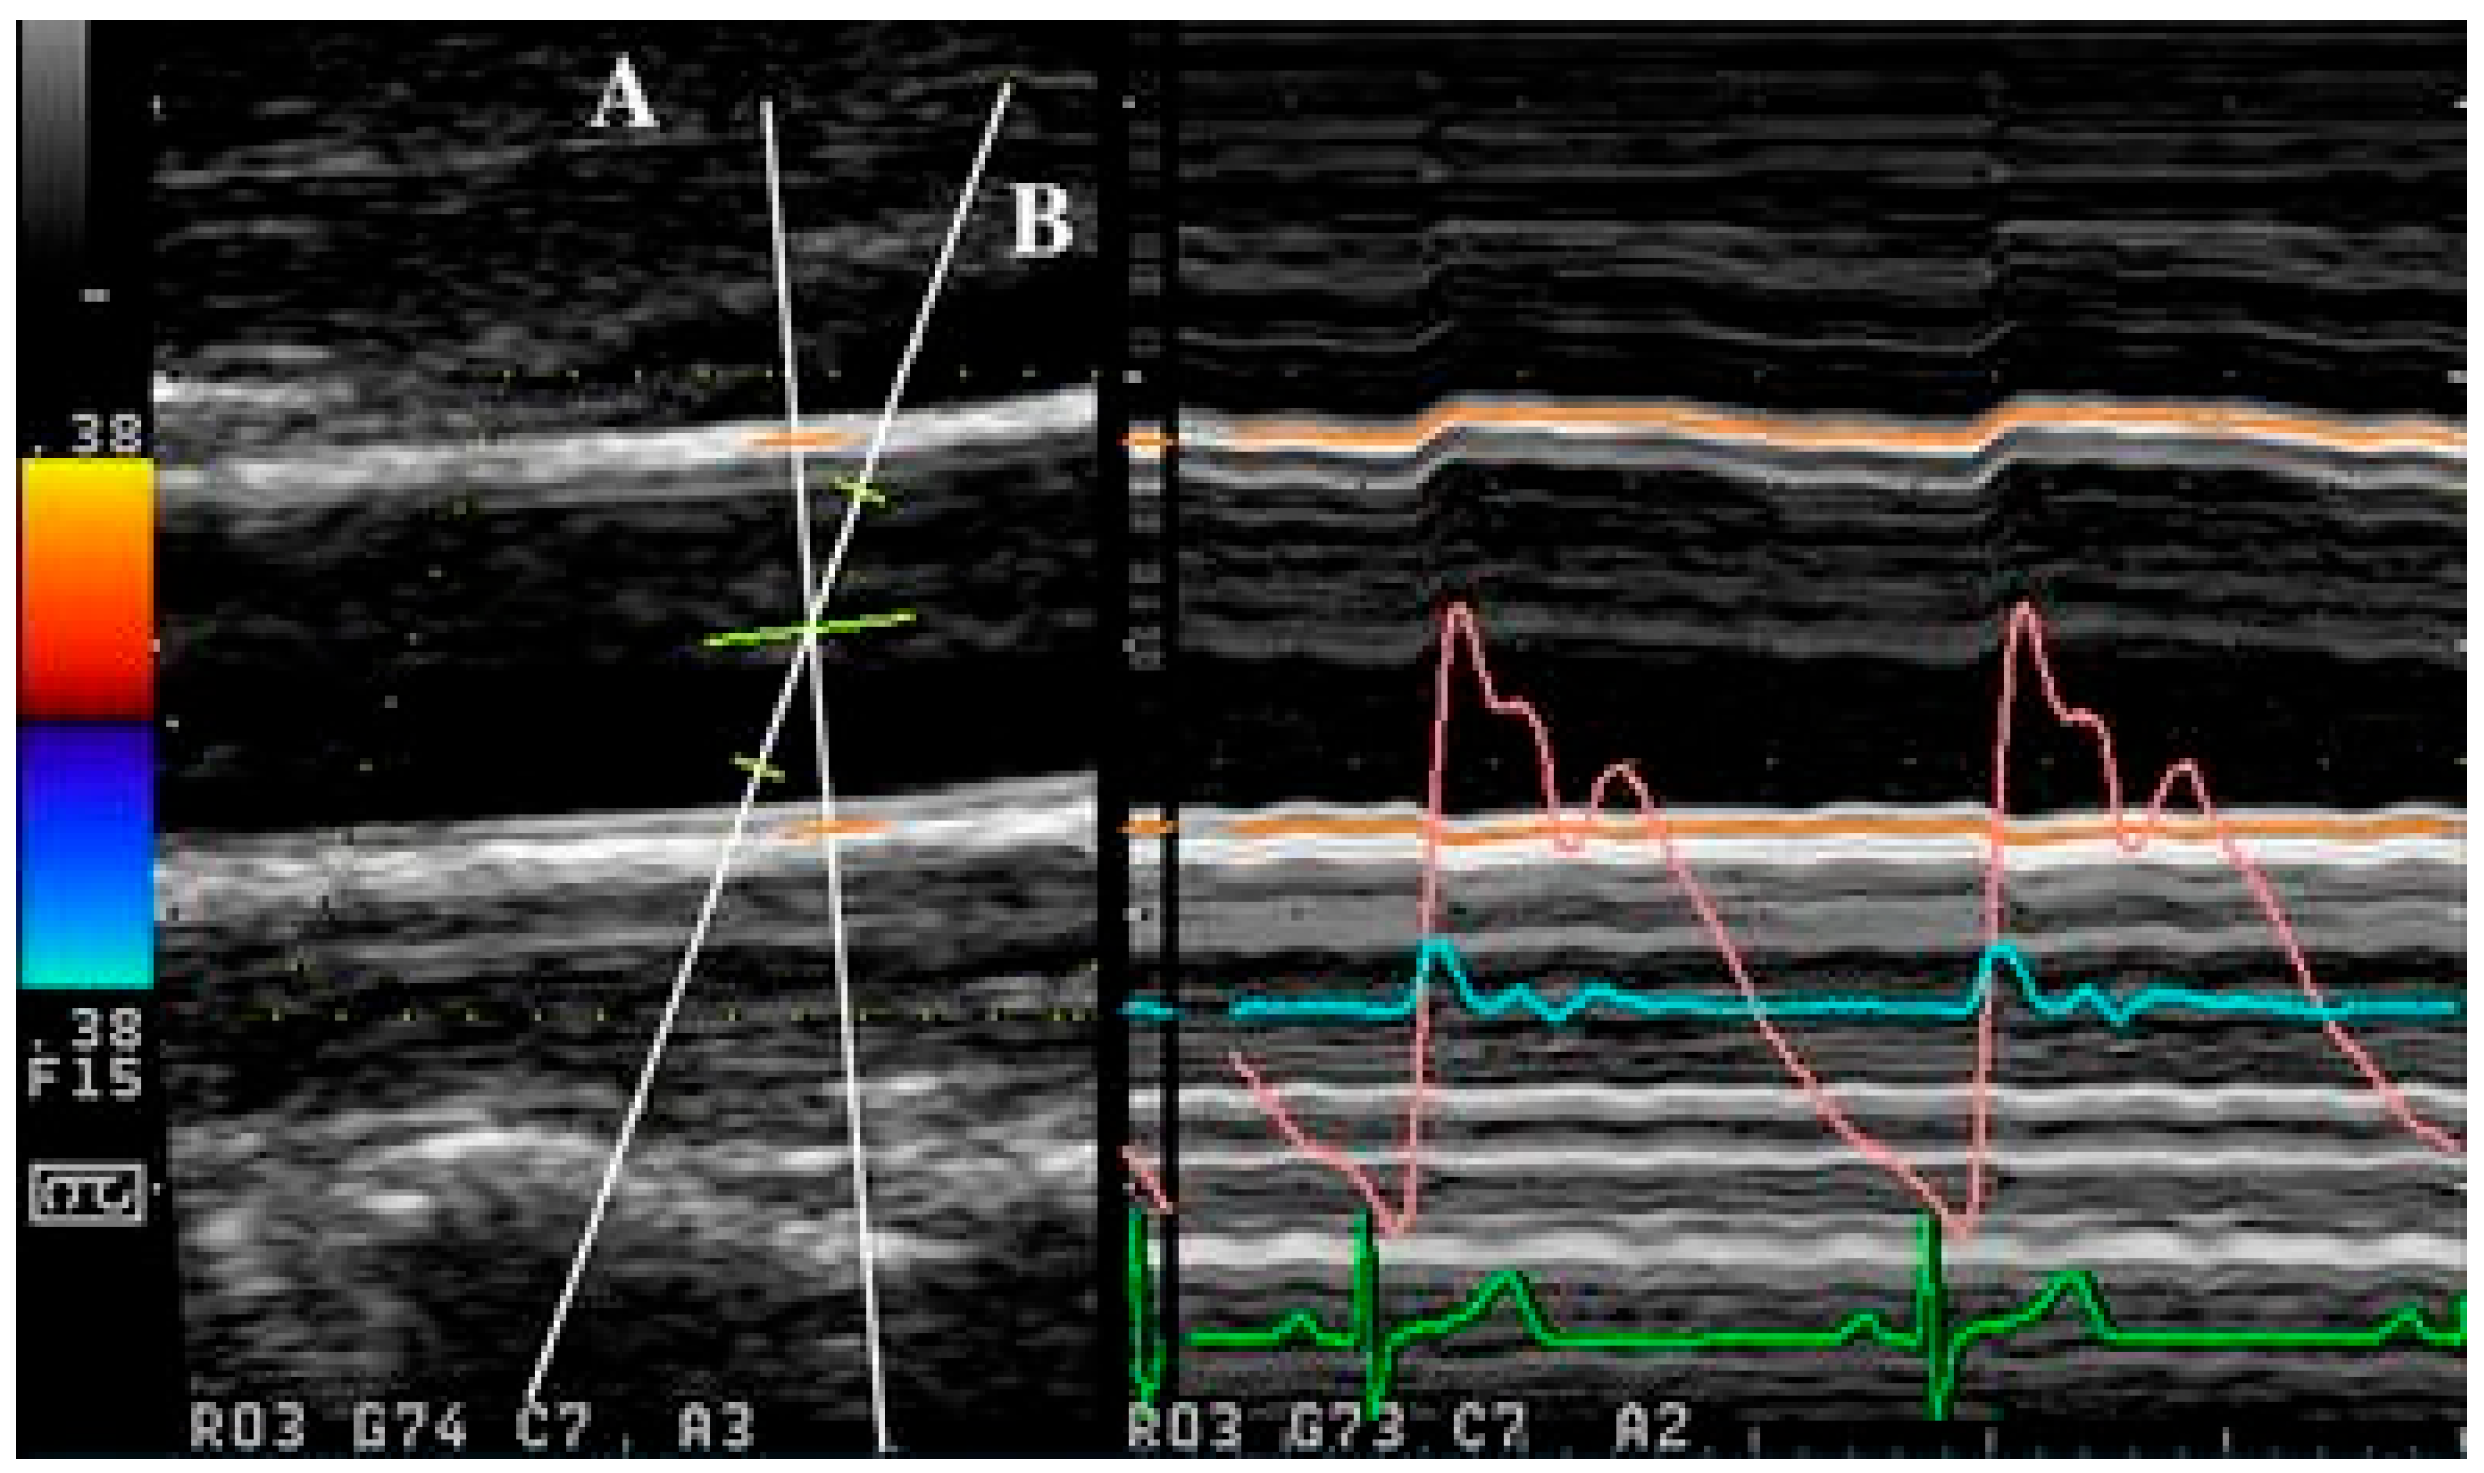

Apart from the use of singular ultrasound beams, as with the abovementioned methods, simultaneous acquisition can also be achieved with the use of multiple ultrasound beams, as demonstrated in [155,156]. In multiple beam acquisition, colour Doppler is used to obtain the blood flow velocity while diameter changes were measured using M-mode. The system consists of both the colour Doppler system and an echo-tracking subsystem that can use different ultrasound beams for velocity and diameter change, respectively. These beams can be independently manipulated, with an intersection between the beams at the range gate for both diameter and velocity measurement, as shown in Figure 4 [156]. From [155], this method was found to have low variabilities in the maximum velocity and arterial diameter measurements despite the need to manipulate different beams, which thereby supports its reproducibility.

Figure 4.

Simultaneous acquisition with two ultrasound beams (A and B), with overlap at the range gate region (from [156] with permission).